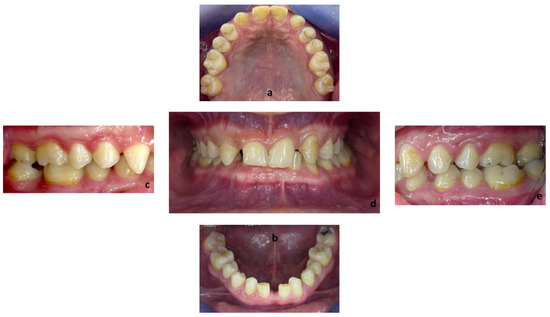

Figure 2.

Endobuccal views: (a) maxillary arch, (b) mandibular arch, (c) right side occlusion, (d) front bite, (e) left side occlusion.

Exobuccal clinical assessment showed a leftward convergence of the facial lines, an asymmetric smile, and the presence of oral corridors. The profile examination showed a lowering of the lower face, an open naso-labial angle, a concave subnasal profile with a reduced cervical-chin distance and a biretrochelia.

Endobuccal clinical assessment revealed dental agenesis of the upper left and right lateral incisors and lower left and right central incisors, generalized small teeth size, infiltrated maxillary grooves, and an amalgam restoration on the occlusal surface of the lower left second molar. Occlusal analysis showed complete overbite, a left unilateral articular inversion on the two upper left molars, an Angle Class I canine and molar on the right side and an Angle Class II canine and molar on the left side. In addition, the anterior overhang is reduced, so the patient is in class II division 2.